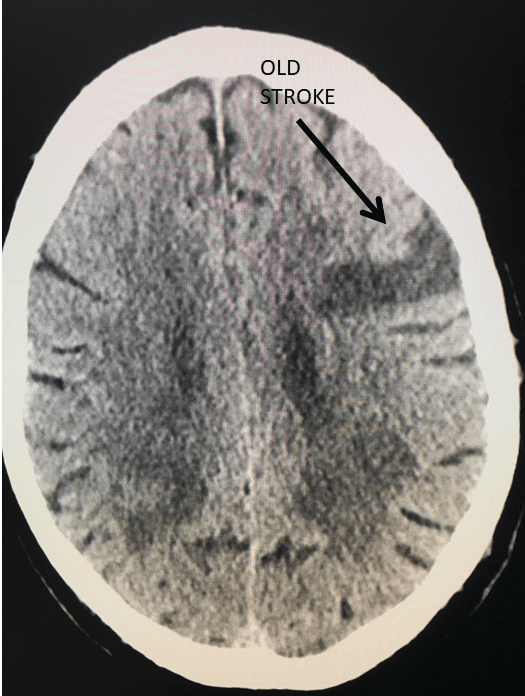

Spine:

Central Cord Syndrome

Author: Yusef Imani M.D., F.A.A.N.S., Read More!